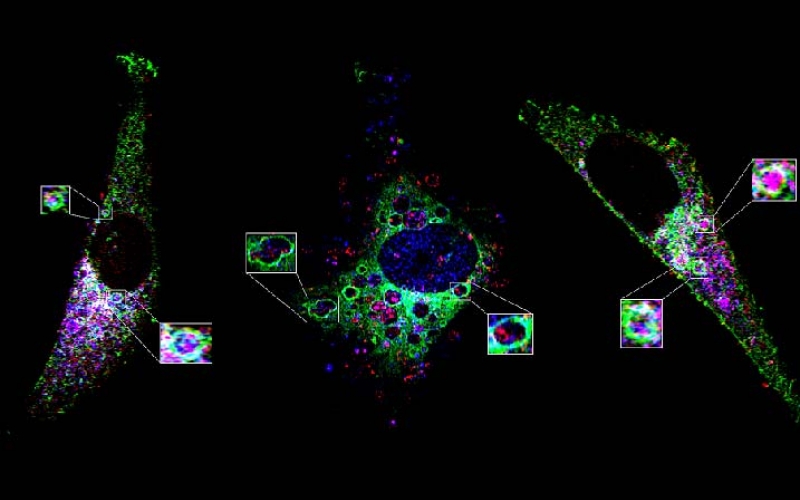

El próximo sábado 12 de abril de 8 a 13 horas, en el aula 101 del IUCBC, se realizará un encuentro con investigadores en biomedicina y profesionales de la salud interesados en el el diagnóstico y prevención de enfermedades, especialmente en el ámbito de la oncología y otras disciplinas médicas.

-Introducción a la Citometría de Tejido y sus Aplicaciones.

-Taller práctico sobre el software StrataQuest: - In-depth characterization de microambientes tumorales usando citometría de tejidos.